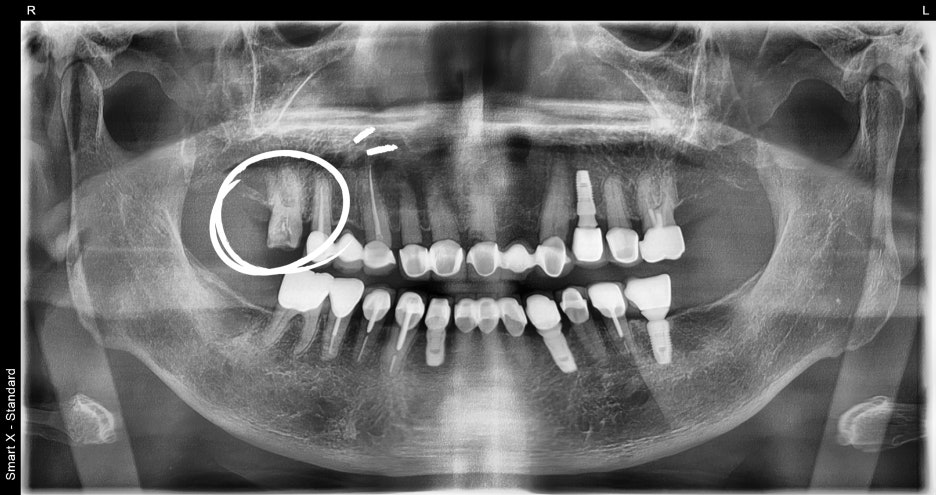

우선 파노라마 촬영과 치석 제거를 진행했습니다.

정밀 파악을 위해 추가로 치근단 엑스레이를 촬영했고, 실제로 치아 뿌리 끝까지 염증이 퍼져 있는 것이 확인되었습니다. 이 단계에서 신경치료 계획을 확정했습니다.